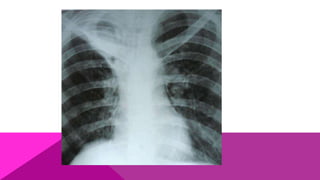

HISTOPLASMOSIS PROGRESIVA

HISTOPLASMOSIS DISEMINADA AGUDA

Es una entidad rara en México; sin embargo, es común en América

del Norte y del Sur. Se presenta a cualquier edad, de preferencia en

pacientes inmunosuprimidos por corticoterapia o por procesos

linfoproliferativos; es también frecuente en niños menores de 10

años, en los cuales es importante porque el curso del padecimiento

es casi siempre mortal a corto plazo.

Dicha fase clínica está constituida por un cuadro respiratorio febril,

con tos constante y poca expectoración, sufren gran pérdida de

peso, anemia y leucopenia.

HISTOPLASMOSIS DISEMINADA CRÓNICA

Es un padecimiento frecuente en América del Sur

(Argentina y Brasil); se presenta sobre todo en

adultos de 40 a 60 años; la sintomatología y datos

clínicos son vagos; hay astenia y pérdida de peso,

acompañados de un cuadro respiratorio crónico

con tos, escasa expectoración y sin hemoptisis,

por lo que se confunde con facilidad con

tuberculosis crónica. En casos graves se pueden

presentar granulomas solitarios, en particular

involucrando piel, mucosas o ganglios linfáticos.

La topografía clínica más habitual es laringe,

faringe, boca, tabique nasal y genitales.

HISTOPLASMOSIS PROGRESIVA HISTOPLASMOSIS DISEMINADAAGUDA Es una entidad rara en México; sin embargo, es común en América del Norte y del Sur. Se presenta a cualquier edad, de preferencia en pacientes inmunosuprimidos por corticoterapia o por procesos linfoproliferativos; es también frecuente en niños menores de 10 años, en los cuales es importante porque el curso del padecimiento es casi siempre mortal a corto plazo. Dicha fase clínica está constituida por un cuadro respiratorio febril, con tos constante y poca expectoración, sufren gran pérdida de peso, anemia y leucopenia.

HISTOPLASMOSIS DISEMINADA CRÓNICA Esun padecimiento frecuente en América del Sur (Argentina y Brasil); se presenta sobre todo en adultos de 40 a 60 años; la sintomatología y datos clínicos son vagos; hay astenia y pérdida de peso, acompañados de un cuadro respiratorio crónico con tos, escasa expectoración y sin hemoptisis, por lo que se confunde con facilidad con tuberculosis crónica. En casos graves se pueden presentar granulomas solitarios, en particular involucrando piel, mucosas o ganglios linfáticos. La topografía clínica más habitual es laringe, faringe, boca, tabique nasal y genitales.